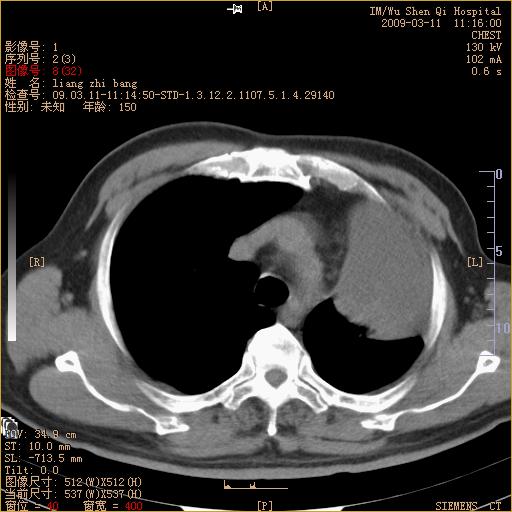

标题: CT18604:男,60岁,咳嗽一月余 [打印本页]

标题: CT18604:男,60岁,咳嗽一月余

1)考虑左肺上叶中央型肺癌并左肺上叶肺不张;建议必要时行纤支镜检查进一步明确诊断。2)左侧胸腔积液。

肺门肿块、支气管开口闭塞伴肺不张及胸水!典型的中心型肺癌变现!

1、左肺上叶中央型肺癌并上叶阻塞性肺不张。

2、左侧胸腔少量积液,右侧胸膜轻度增厚。

左肺们肿块并左肺上叶不张。考虑左肺中心性肺癌并左肺上叶不张及左侧胸腔积液